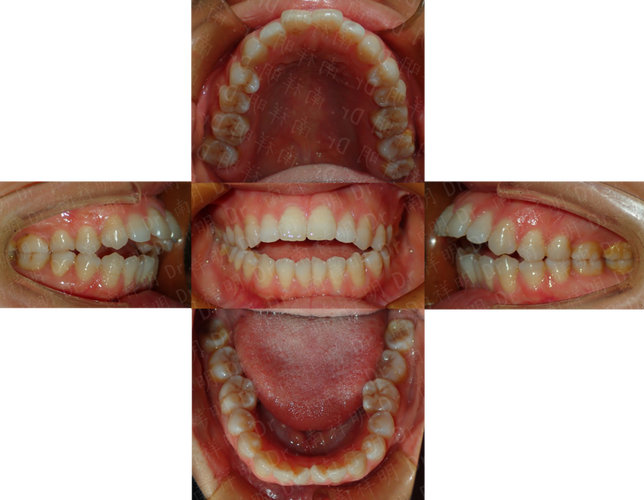

牙齿中线偏移是指上下颌牙齿接触点的连线与面部中线(如鼻尖、人中唇缘连线)不一致,表现为上下中线向左或向右偏离,不仅影响面部对称性,还可能引发咬合紊乱、牙周问题等,本文将从原因、危害、矫正方法及注意事项展开分析。

中线偏移的危害不仅限于美观:面部不对称可能影响自信,微笑时中线偏差尤为明显;咬合功能上,长期单侧咀嚼可能导致颞下颌关节紊乱(如弹响、疼痛),甚至引发牙齿磨耗、牙周创伤。